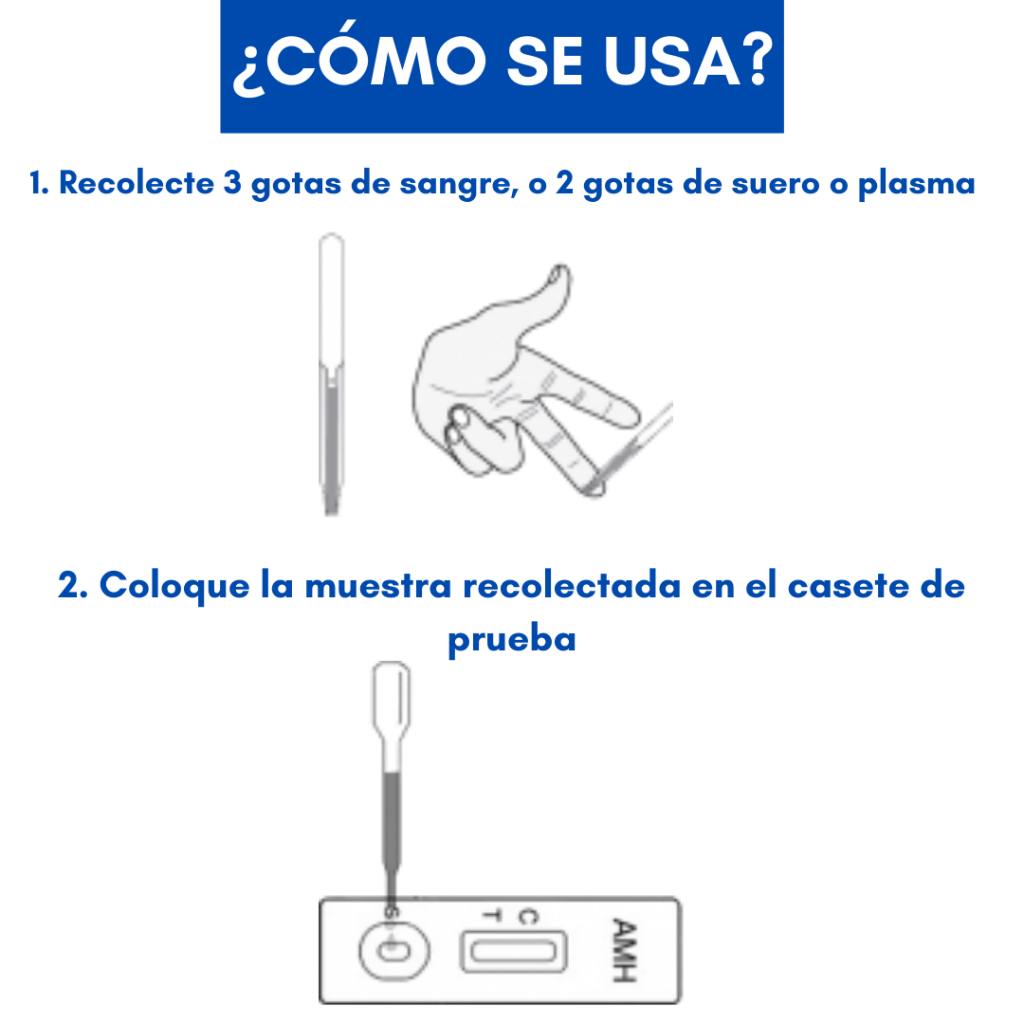

Aquí es donde Hemoglinet redefine el panorama del diagnóstico y control de la diabetes. Esta innovadora prueba de hemoglobina glicosilada (HbA1c) elimina la necesidad de equipos sofisticados y costosos.

Con solo unas gotas de sangre, Hemoglinet permite una detección cuantitativa in situ, lo que significa que el análisis puede realizarse en cualquier lugar, desde un consultorio médico hasta un entorno rural, sin la infraestructura de un laboratorio tradicional.

Si la prueba de Hemoglinet muestra dos líneas encendidas, indica que el nivel de hemoglobina glicosilada del paciente está por encima del 6.5%, un claro signo de descontrol o diagnóstico de diabetes que requiere atención inmediata.